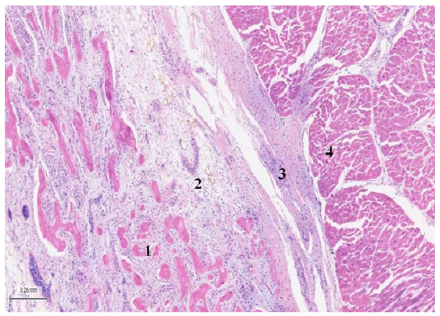

Figure 5: (Bovine heart), H&E (25x). The image shows plexuses associated with fibro-chondroid trabeculae and the myocardium. 1: bone trabeculae. 2: plexuses. 3: fibroconnective tissue. 4: myocardium.